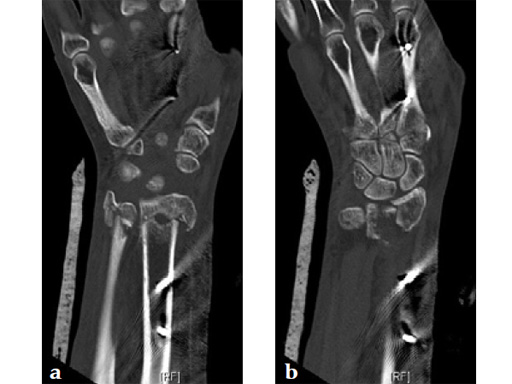

Fig 2a-b Comparison of anatomical bend and screw placement of volar rim DR plate (a) and DR juxta-articular plate (b).

The anatomical plate design allows for very distal plate placement. CT scans were used to verify the fit of the precontoured plate. Bendable outriggers aid in adjusting the precontoured plate to specific anatomical need and individual variations.

The second distal screw row provides for superior fixation stability of fragments, eg, radial styloid, and especially the most ulnar corner of the lunate fossa.